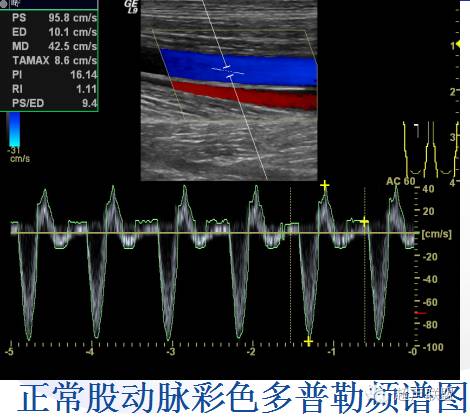

一、正常肢体动脉超声表现与血流频谱:

2DE:动脉管腔清晰,管壁平滑,较伴行静脉管壁厚,管壁分三层:内膜、中层、外膜,呈强弱强三层线状回声。

CDFI:管腔充盈良好,呈搏动性。

PW:肢体动脉血流频谱呈高阻力三相型频谱,即收缩期的高速上升波(心室快速收缩射血形成),舒张早期的短暂反流波(舒张早期心室内压迅速下降,主动脉瓣关闭,血液反流所致),舒张中晚期的低速上升波(舒张中晚期动脉管壁弹性回缩形成)。